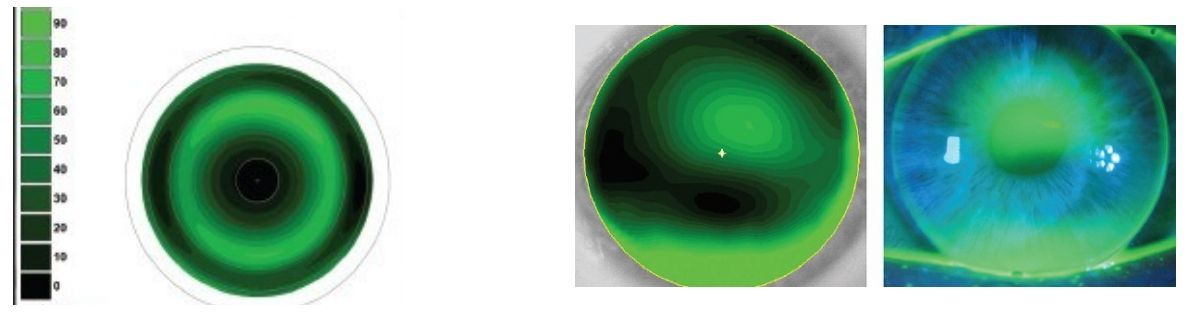

OK镜

验配前检查角膜避免干眼和圆锥角膜禁忌症;验配中,能计算所需镜片的直径,基弧等,具备镜片佩戴规划辅助系统,一次选片成功率高于90%,角膜地形图测量以及角膜地形图变化趋势分析。

可视化验配——断层扫描

深度可以纳米为单位进行测量,可显示密度。

可进行角膜镜片:360°成像;前后表面曲率半径测量;镜片偏心距离、倾斜角度测量。

可进行Ortho-K CL:直径计算;戴片前预估戴片后镜片角膜贴合程度视轴方向角膜镜片空隙量等;多角度观察。

可拖拽镜片到角巩膜上,可视化验配。